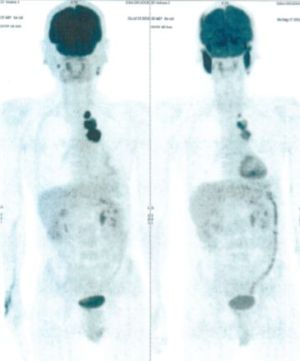

CASE NO: 1 - A FEW MONTHS LATER

A few months after successful treatment for hepatocellular carcinoma, and partially successful for stomach cancer, the PET/CT scan showed the stomach cancer becoming very active, with several metastases to the parts of the liver not previously involved by hepatocellular carcinoma. After a few treatment, all the active stomach cancer lesions in the stomach and in the liver went into remission.

CASE NO: 2 (HEPATOCELLULAR CARCINOMA)

A 40+ man with hepatocellular carcinoma, an incurable cancer. After 2 treatment, the activity of the hepatocellular carcinoma is less.

CASE NO: 2 (HEPATOCELLULAR CARCINOMA) - After a few more treatments

After another few treatment, the activity of the hepatocellular carcinoma is much less. The patient never came back for further treatment, but this case, and case no: 1, shows that incurable hepatocellular carcinoma, often seen in hepatitis B and C patients, can be cured.